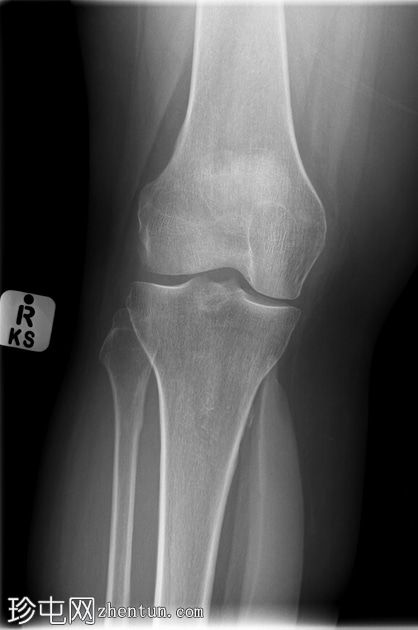

超声

横断面

可见皮下、肌外软性硅胶小腿植入物。植入物包膜局部破裂/撕裂,局部凝胶渗漏,并出现炎症反应,多普勒超声检查显示充血。未见边界清晰或包膜完整的脓肿形成。